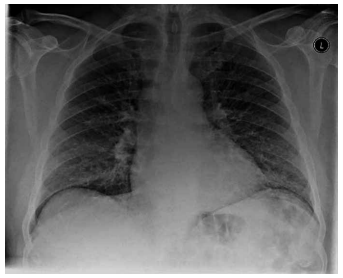

Homem de 50 anos é internado com quadro de tosse há

duas semanas, com expectoração clara associada a febre, anorexia e mal-estar. Não há antecedente mórbido,

mas é fumante atual de vinte cigarros por dia há vinte

anos. Ao exame físico: SatO2: 91% em ar ambiente; taquipneico; há sibilos bilaterais leves à ausculta. Exames

séricos à chegada: proteína C reativa: 170 mg/L (normal:

até 10); hemoglobina: 11,7 g/dL; neutrófilos: 24.000/mm3.

A radiografia de tórax do paciente na admissão é mostrada a seguir:

(Arquivo pessoal; imagem usada com autorização)